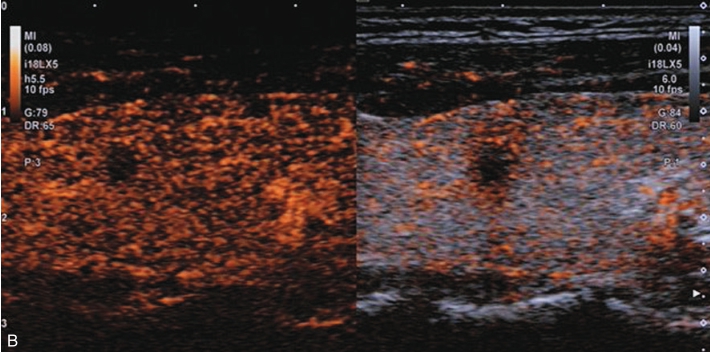

注入造影剂后甲状腺左叶囊实性结节内始终呈无增强,边界清晰,结节周围甲状腺被膜完整,见图1-3-4、ER1-3-2。

(1)周围囊壁呈均匀高增强,边界清,内部始终无造影剂灌注。

(2)结节周边被膜连续且完整。

图1-3-4 甲状腺囊肿伴出血超声造影图

A.注入造影剂后17s图像;B.注入造影剂后28s图像,结节内部始终呈无增强